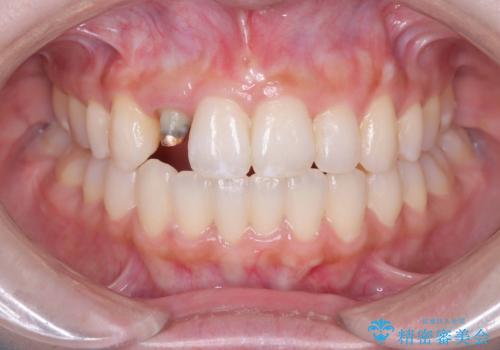

- 「前歯の見た目が気になる」を主訴に来院された患者様です。

オールセラミッククラウンで治療を行いました。

被せ物と歯の境の位置が歯肉の上に設定されており、それによって審美障害が起きていました。

歯と被せ物の境を歯肉縁下0.5㎜に設定して形成を行いオールセラミッククラウン(スペシャル)で治療を行いました。